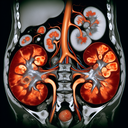

МРТ нирок

Магнітно-резонансна томографія (МРТ) нирок — це безпечний і неінвазивний метод обстеження, який використовує магнітне поле та радіохвилі для отримання детальних зображень нирок. Ось як підготуватись до процедури: 1. **Консультація з лікарем**: Перед обстеженням повідомте лікаря про наявність алергій, вагітності, клаустрофобії або встановлених медичних імплантів (наприклад, кардіостимуляторів)...